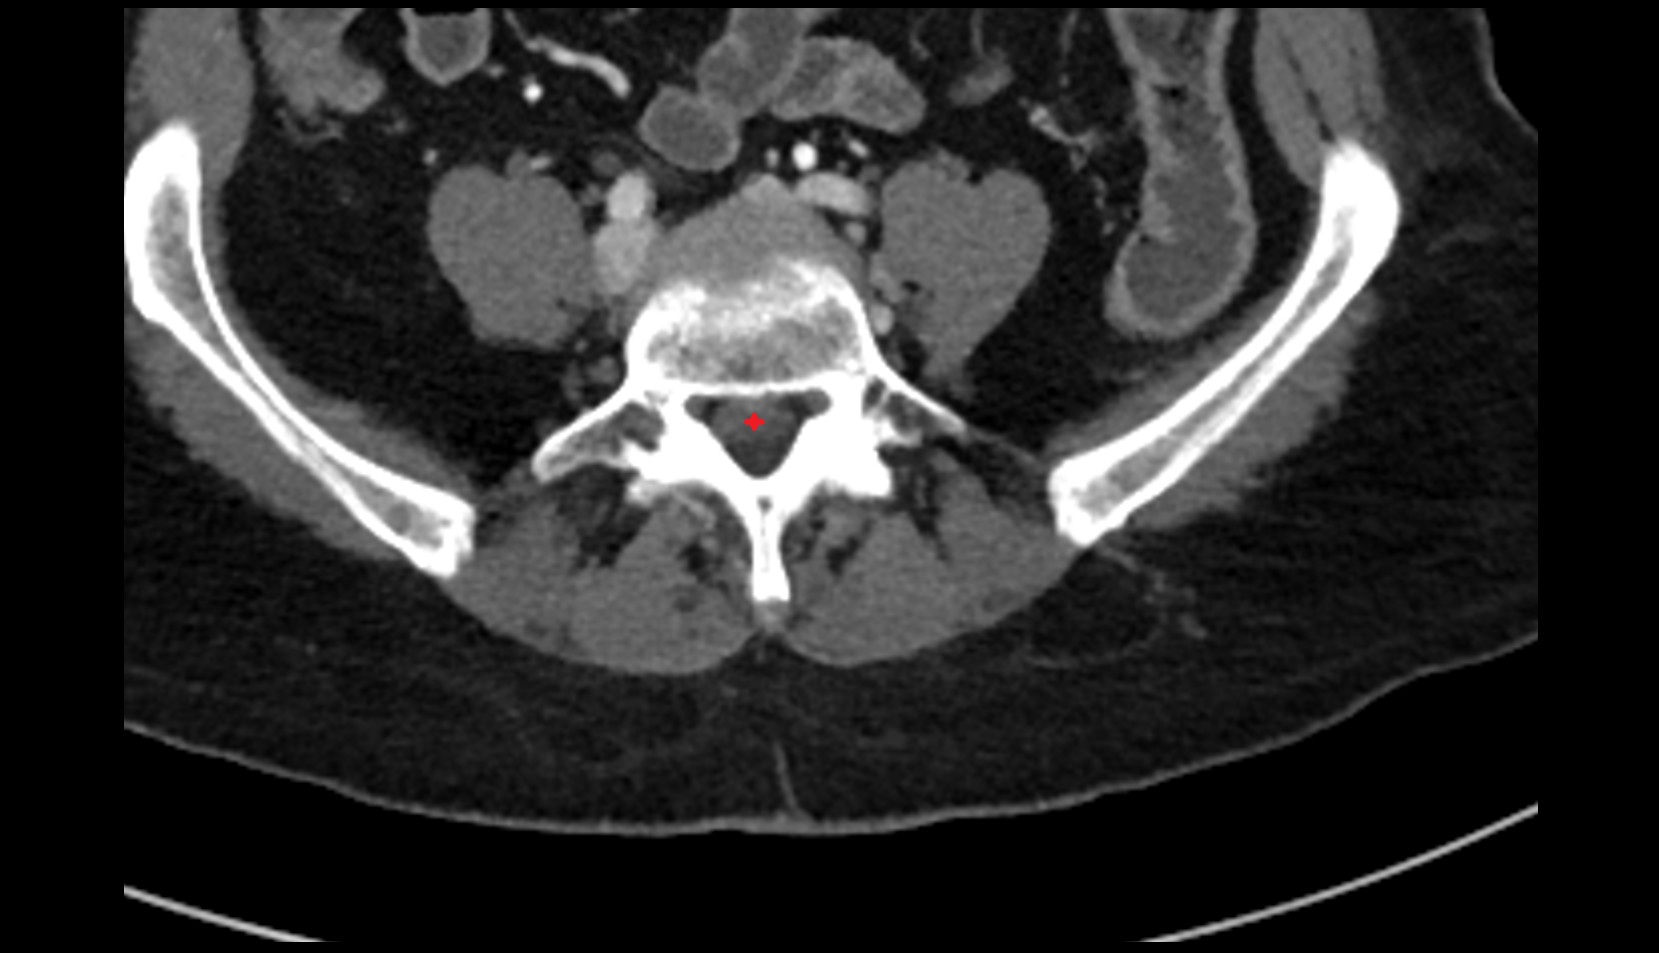

- Cauda equina

- Conus medullaris